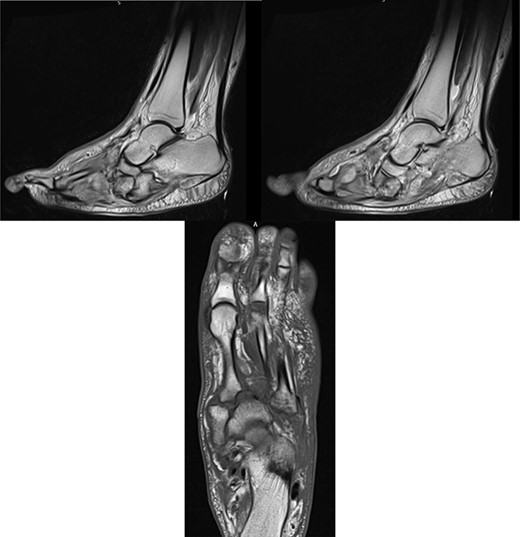

A 41-year-old female, with a background of Type 1 Diabetes Mellitus (T1DM), previous diabetic foot infection and peripheral neuropathy, presented acutely with a hot, swollen and erythematous left foot. Ten days prior, she sustained a fall whilst walking. The patient denied injury, swelling or pain at the time, though she presented to the emergency department (ED) 2 days following the fall with a new-onset foot swelling. Initial imaging with plain film X-ray, as well as blood tests, was unremarkable (Fig. 1), and she was discharged from the ED. A plantar blister appeared over the following days, with subsequent worsening of foot swelling and erythema over a 10-day period, culminating in her acute presentation (Fig. 2).

At this presentation, plain film X-ray revealed complete fracture dislocations of the second to fifth tarsometatarsal joints, involving the lateral, middle and medial cuneiform bones of the left mid-foot (Lisfranc fracture dislocations; Fig. 3). This was correlated with bone CT (computed tomography) and MR (magnetic resonance) imaging, with interval changes noted to be of rapid onset (Fig. 4).

MR images, correlating plain film findings of acute mid-foot destructive changes; typical ‘rocker bottom’ appearance of plantar aspect of foot is seen.